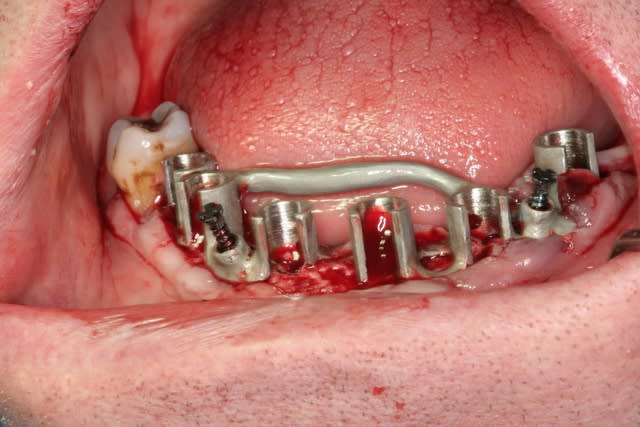

bon, et bien c'est fait!

durée...de 9h30 à 17h30...çà c'est assez épuisant...

ne me dites pas que les vis d'ostéosynthèses sont pas vissées à fond...c'était le "grain de sable" de la journée, vis commandées par posit, mais pas les bonnes livrées...donc système D car tournevis inutilisable

heureusement, les guides sont "superlatifs": quelle précision d'ajustement osseux!!! à tel point qu'au maxillaire on aurait bien pu totalement se passer des vis d'ostéosysthèse...

ah, oui, j'allais oublier au maxillaire 8 legacy3 diamètre 3.7mm et en 13 de long (sauf 22 en 11.5mm)

mandibule 6 implants de 13mm et 3.7mm de diamètres (sauf 36 et 45 en 4.2mm/13)